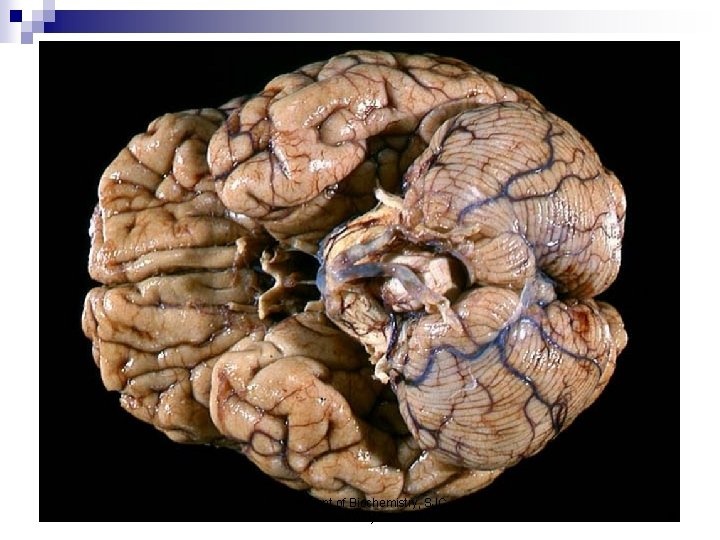

Brain of Human and Different Animals Department of Biochemistry, SJC, Trichy 2